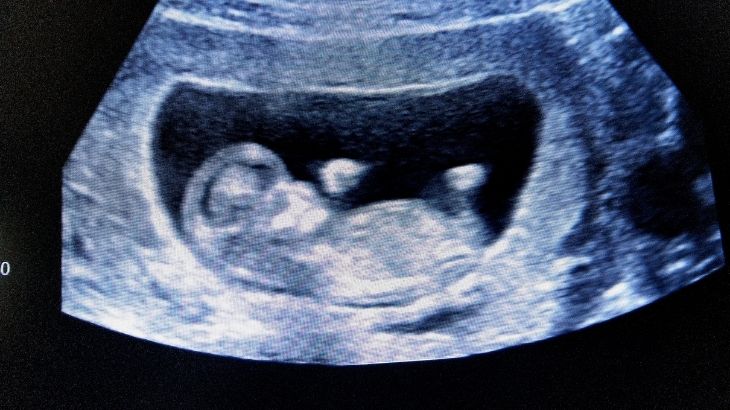

Baş, vücut, kollar ve bacaklar net şekilde seçilebilir. Bebek hareket etmeye başlar ve bazen ellerini yüzüne götürebilir.